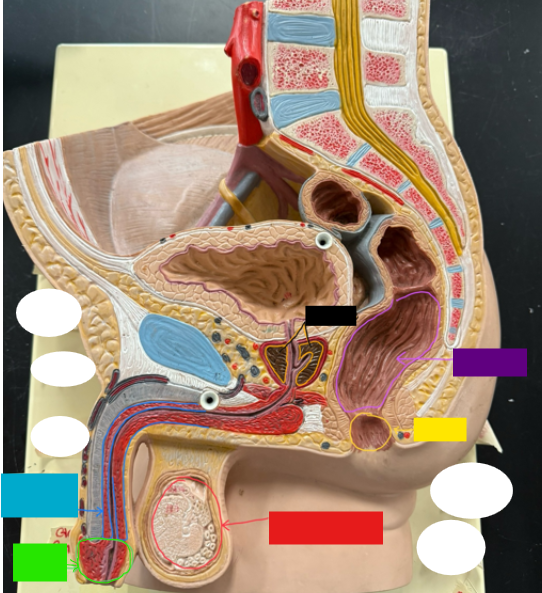

What is the name of the blue box?

Corpus spongiosum

What is the name of the light green box?

Glans penis

What is the name of the red box?

Seminiferous tubules

What is the name of the black box? X2

Prostate

What is the name of the purple box?

Rectum

What is the name of the yellow box?

Anus

What is the name of the red box?

Scrotum

What is the name of the orange box?

Corpus cavernosum

What is the name of the light blue box?

Spongy urethra

What is the name of the red box?

Prostatic urethra

What is the name of the pink box?

Ejaculatory duct

What is the name of the yellow box?

Membranous urethra

What is the name of the brown box?

Testis